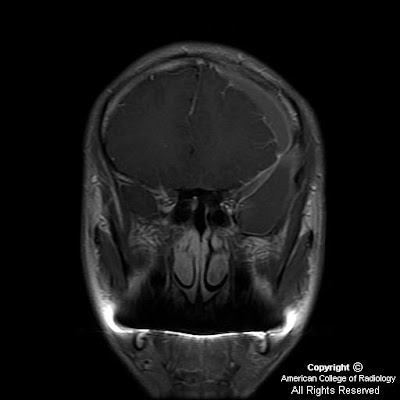

Findings

Heterogeneously enhancing mass centered at the junction of the left nasal cavity and ethmoid sinus has eroded through the cribriform plate and extends into the anterior cranial fossa. Sharp interface between the mass and the brain parenchyma, with mass-effect and vasogenic edema in the left frontal lobe. Left orbit medial wall has been eroded, and the extraconal mass has mass-effect on the left medial rectus with the fat plane between the mass and the muscle intact. Mass extends posteriorly to the margin of the left sphenoid sinus Bilateral frontal sinuses are fluid filled with the mass minimally extending into the inferior portion of the right frontal sinus. Ethmoid sinuses are completely occupied by the mass. Right maxillary and sphenoid sinuses are clear. Left maxillary sinus is almost completely fluid filled, and the left osteomeatal unit is completely obstructed by the mass.